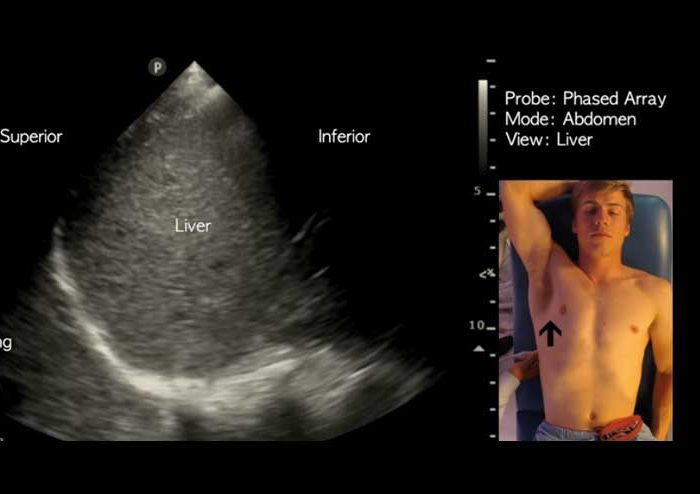

Ultrasound employs technology that sends sound waves into the body, recording the reflection. Ultrasound is also used for a detailed assessment of blood flow (‘Doppler ultrasound’) and for views of soft tissue and anatomical body structures.

Ultrasound is safe, painless and the first line investigation of choice for gallbladder and gynaecological abnormalities.